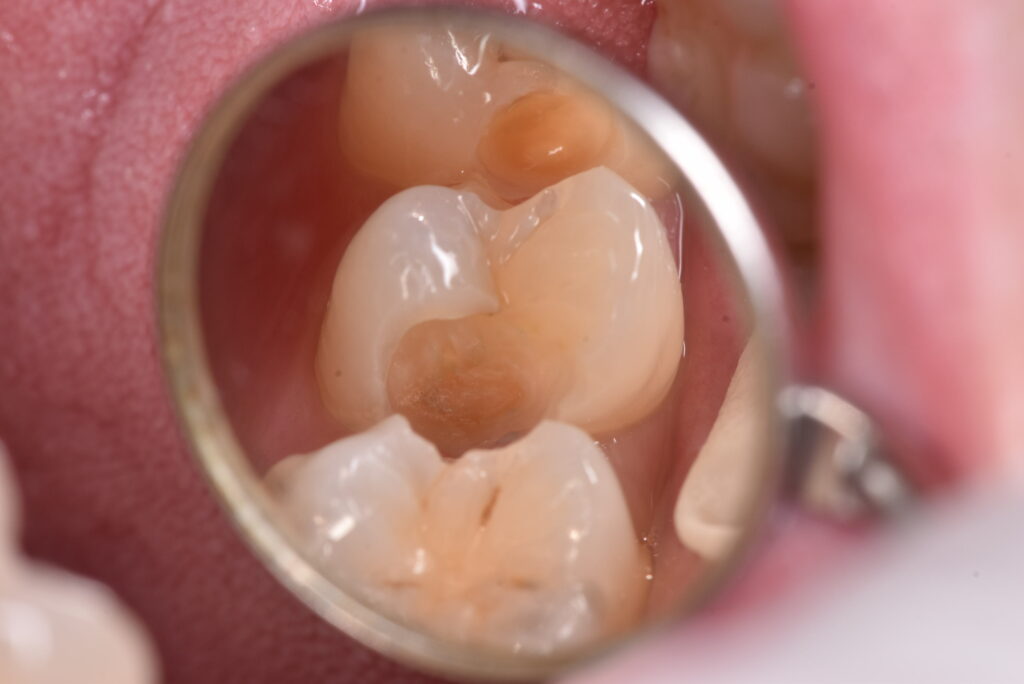

間の部分にむし歯があるのですが、おわかりでしょうか?「なにもないよ!」と言う方の方が多いのではないでしょうか?では、ここを削っていったらどうなったのか、下の写真をご覧ください。

神経に到達する寸前くらいの、深いむし歯が広がっていました。これまでのブログでも書いた通り、今回も症状はありません。では、問題なかったのか?でいうと、答えは上の写真に示した通りです。

上の写真を見返したときに、ご自身がどう感じるか?をよくよくお考え下さい。

歯科医師側にゆだねれば、それは基本的には「処置をする」という意味になってきます。しかし、上の状況になってもなお、歯を削ることそれ自体が問題、と感じている方もおられるようです。そのようにお感じの方は、近隣の歯科医院の評判をよく伺ってください。中には必ず、何が何でも処置をしない歯科医院があるはずです。悪いところを治したい、と思っているのか、口の中を処置することが悪なのか、この価値観の違いがよくある歯科医師と患者間のトラブルの原因となっております。